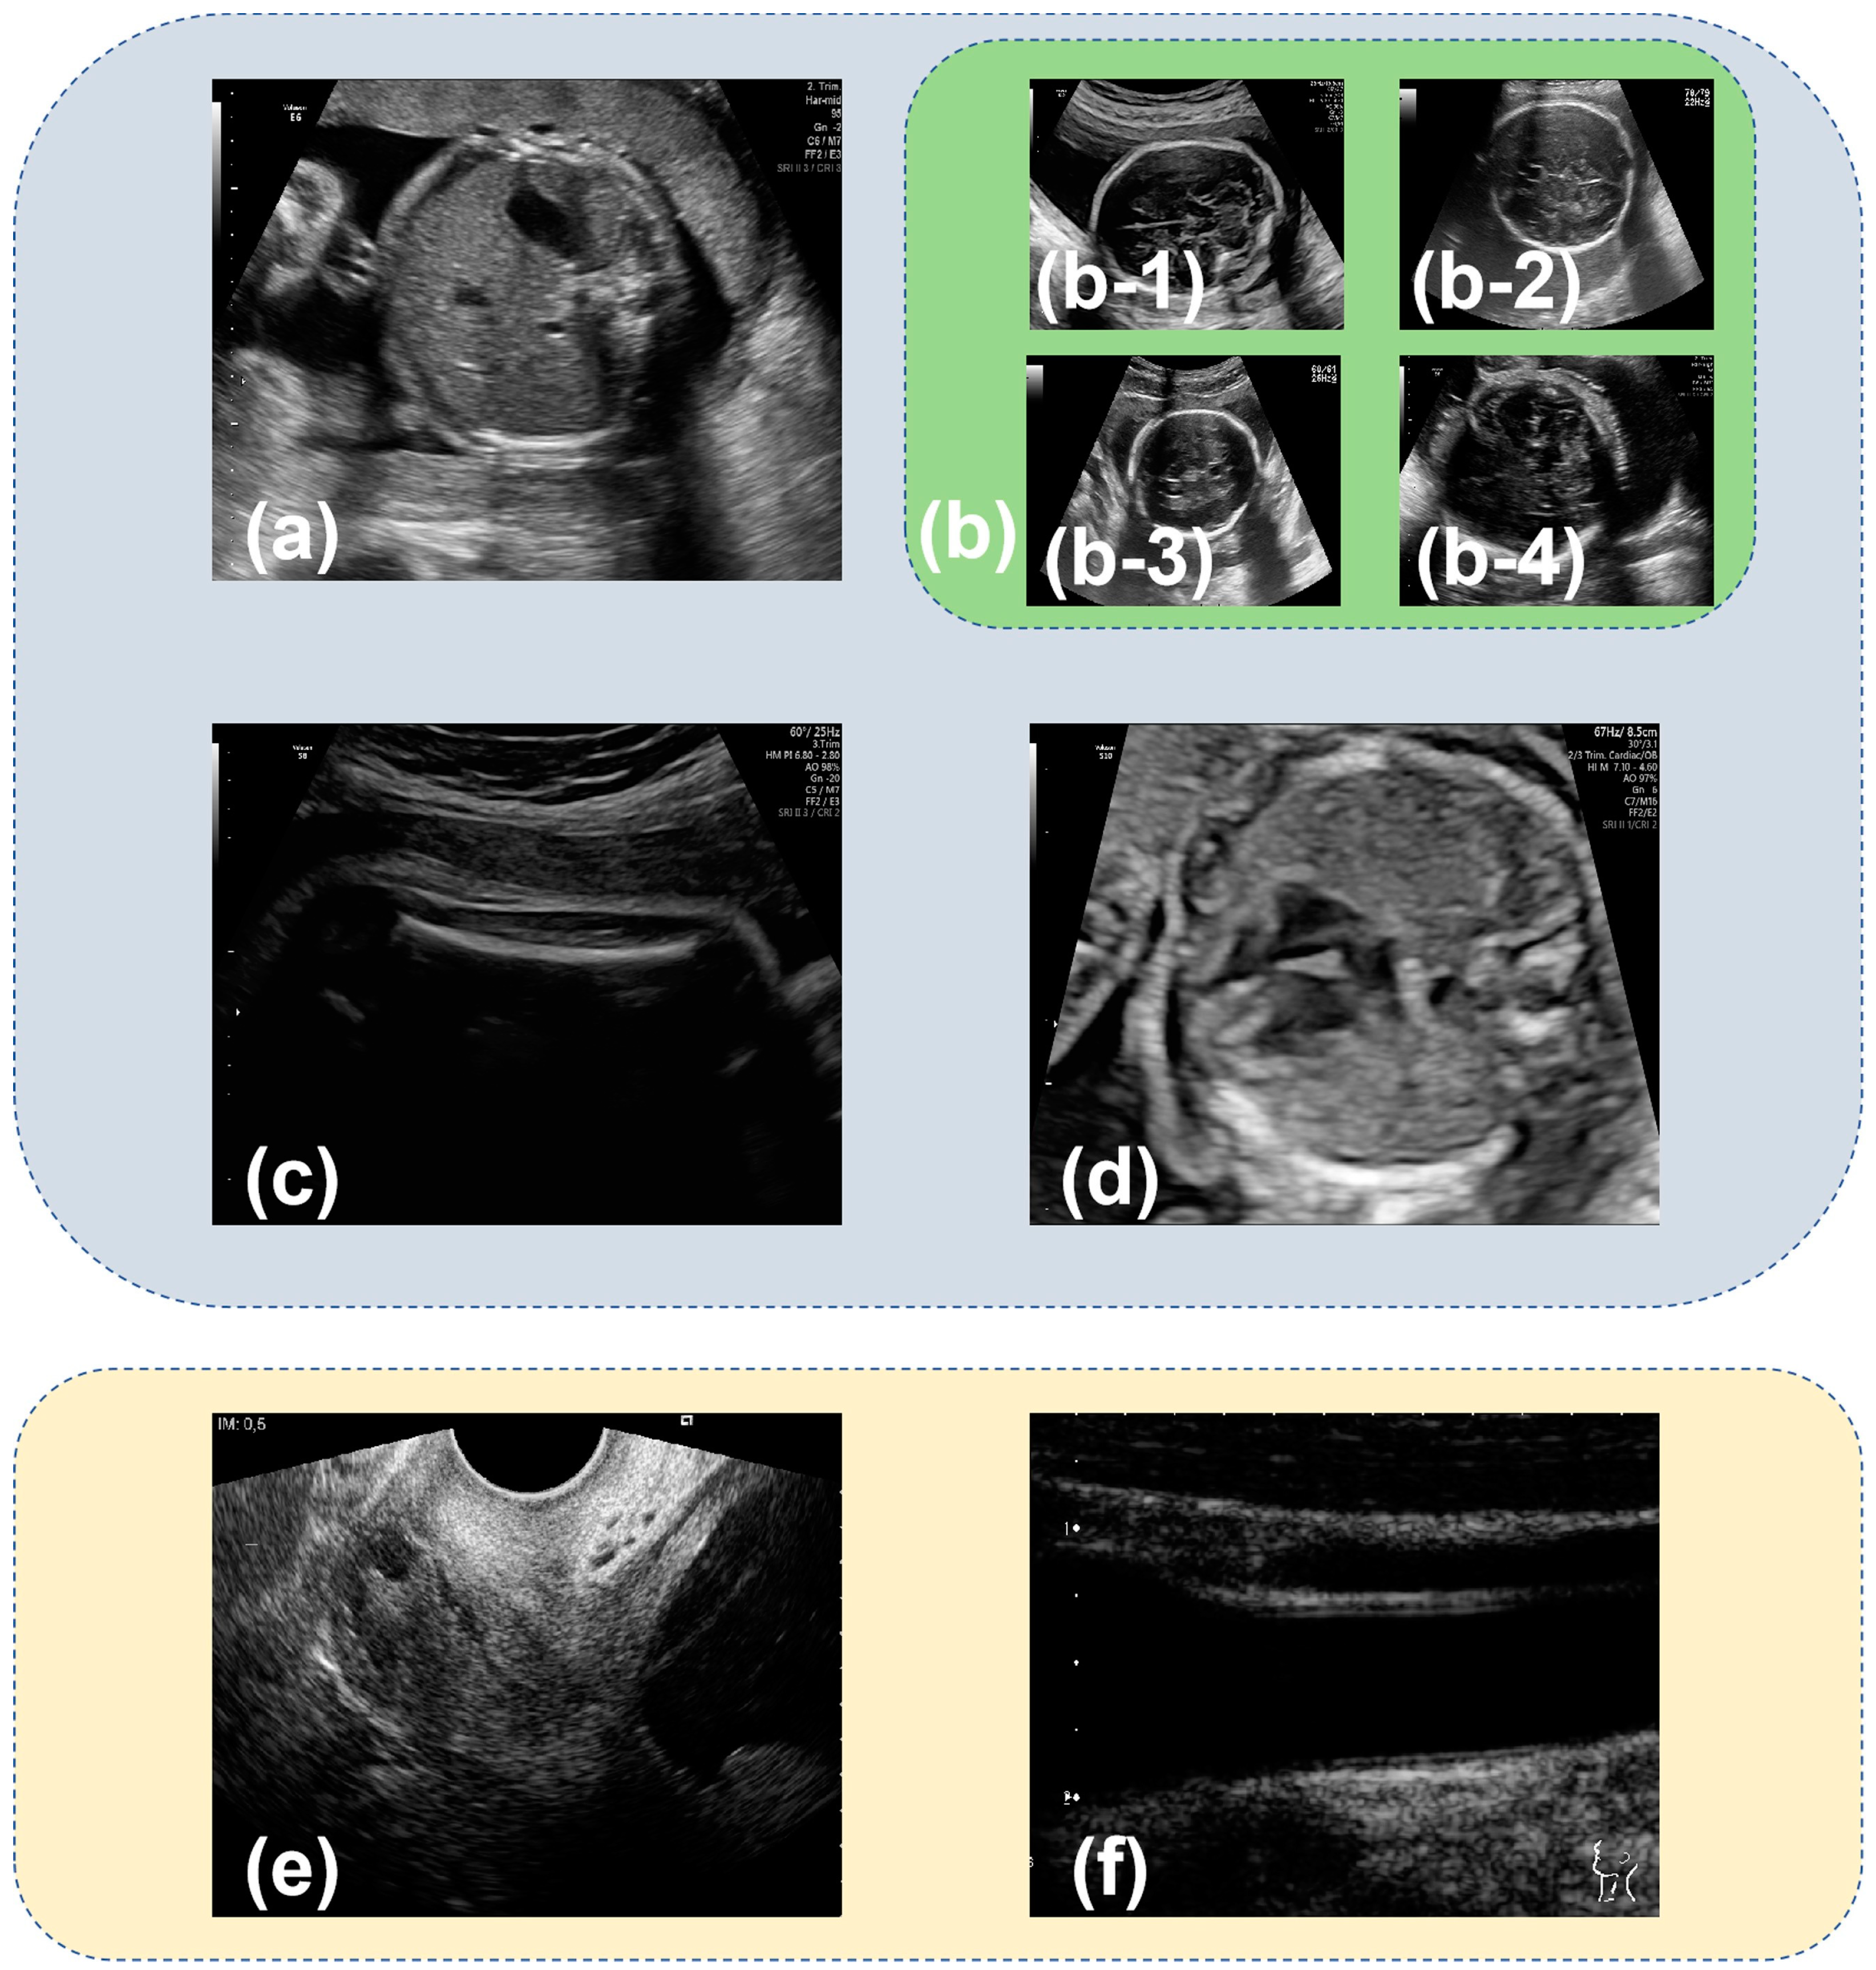

The open-access dataset used in this paper was made public in 2020 by Burgos-Artizzu et al. [22]. The 12,400 images in the dataset were manually labeled by an expert maternal fetal clinician and divided into 6 categories: fetal abdominal standard plane (Figure 1a), fetal brain standard plane (Figure 1b), fetal femur standard plane (Figure 1c), fetal thorax standard plane (Figure 1d), maternal cervix (Figure 1e), and other (Figure 1f). The fetal brain standard plane was further categorized into fetal trans-ventricular standard plane (Figure 1(b-1)), fetal trans-thalamic standard plane (Figure 1(b-2)), fetal trans-cerebellum standard plane (Figure 1(b-3)), and other brain standard plane (Figure 1(b-4)). The dataset was randomly divided into training, validation, and testing sets in a ratio of 8:1:1, resulting in 9916 images for training, 1243 for validation, and 1241 for testing. The specific number of images used for classifying six and nine categories is outlined in Table 1 and Table 2.

Figure 1.

Representative images from Burgos-Artizzu’s dataset [22] depicting various fetal ultrasound standard planes: (a) fetal abdominal standard plane; (b) fetal brain standard plane; (b-1) fetal trans-ventricular standard plane; (b-2) fetal trans-thalamic standard plane; (b-3) fetal trans-cerebellum standard plane; (b-4) other brain standard plane; (c) fetal femur standard plane; (d) fetal thorax standard plane; (e) maternal cervix; and (f) other. (a–f) are samples for six categories classification. (a–f) are samples for nine categories classification.